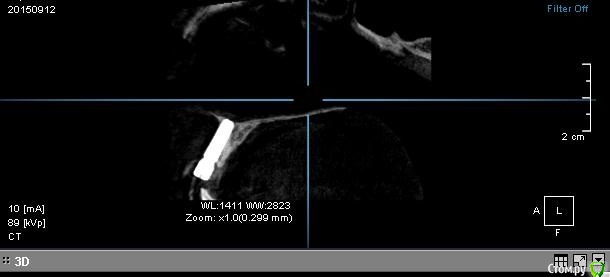

Ната-ли Опубликовано 16 сентября, 2015 Поделиться Опубликовано 16 сентября, 2015 Всем удачного дня!Совсем не знаю как мне быть ?! Просверлили нечаянно корень зуба, пришлось ставить имплант Astra Tech. Имплант стоит уже год. Болел пол года при эмоциональных , физических, психологических нагрузках ))) Имплан мой очень не любил спорт и горячий душ))) Но если просто лежать на диванчике, то имплант чувствовал себя прекрасно. Сумомед и кетанов стали моими неразлучными друзьями.) Кстати, нос тоже болел...наверное и нос как-то нечаянно задели имплантом))) Сейчас вроде по-легче.... Сделала снимок импланта в 3д. Когда расшифровали, я была в полном стрессе... Всё содержимое снимка, с моим вращающем черепом загрузить не получается...вот сделала скрин...(вид с боку)Имплант на 11-ом зубе , впереди держится только за слизистую, судя по снимку кости нет ...куда делась не знаю...то ли ушла куда-то, то ли так имплант вкрутили ...мимо кости???Выпиливать имплант не хочется....я же ещё часть кости потеряю ? Имплант беспокоит иногда (ноет, пульсирует), но я уже привыкла. Десна ушла вверх, может пластику десны сделать? (Хотя ни у кого из моих знакомых ни чего не получилось, слизистая, взятая с нёба , отваливалась вместе с нитками.Десна становилась ещё хуже и выше.)Не думаю, что "нарощенная" десна укрепит имплант ))),... но будет по-эстетичнее какое-то время...но потом десна вероятно снова поднимется, держаться-то ей не на чем )))Короче, что делать с десной не знаю...ПО поводу импланта ??? Думаю поставить пока коронку и посмотреть что будет дальше ? Я передними зубами есть ни чего не буду ))) просто для красоты хотя бы))) И буду ждать когда имплант сам выкрутиться ))) Или как ??? Ссылка на комментарий